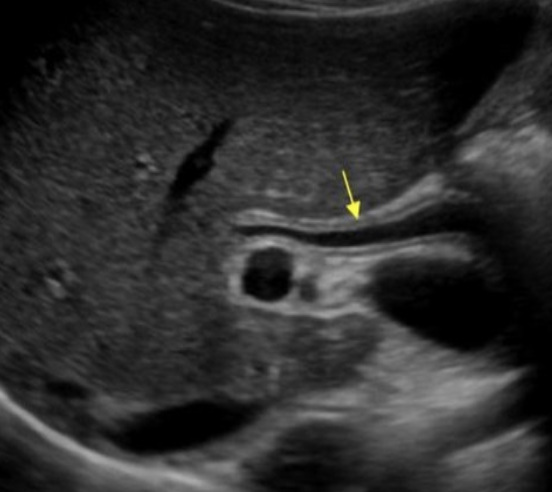

Mirizzi Syndrome → obstruction of CHD by secondary inflammation due to stone impacted in cystic duct

2D US: cholecystitis with large stone in cystic duct, cystic duct stump with large calcified stone, intrahepatic dilation, normal CBD

color doppler:

DDX: cholangiocarcinoma, choledocholithiasis/cholelithiasis